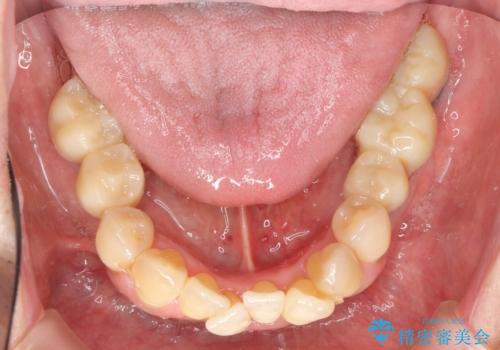

インプラント治療を併用した全顎歯周病治療

全顎的治療について

工程も多く、治療期間も長くなりがちですが、しっかりと通っていただいたおかげで安定した噛み合わせで食事を楽しむことができるようになりました。

メンテナンスも定期的に行うことで安定した状態を保っています。